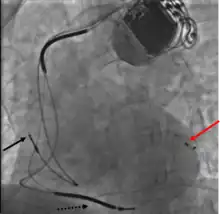

Biventricular pacing

Cardiac resynchronization therapy (CRT) is used for people with heart failure in whom the left and right ventricles do not contract simultaneously (ventricular dyssynchrony), which occurs in approximately 25–50% of heart failure patients. To achieve CRT, a biventricular pacemaker (BVP) is used, which can pace both the septal and lateral walls of the left ventricle. By pacing both sides of the left ventricle, the pacemaker can resynchronize the ventricular contractions.

CRT devices have at least two leads, one passing through the vena cava and the right atrium into the right ventricle to stimulate the septum, and another passing through the vena cava and the right atrium and inserted through the coronary sinus to pace the epicardial wall of the left ventricle. Often, for patients in normal sinus rhythm, there is also a lead in the right atrium to facilitate synchrony with the atrial contraction. Thus, the timing between the atrial and ventricular contractions, as well as between the septal and lateral walls of the left ventricle can be adjusted to achieve optimal cardiac function.